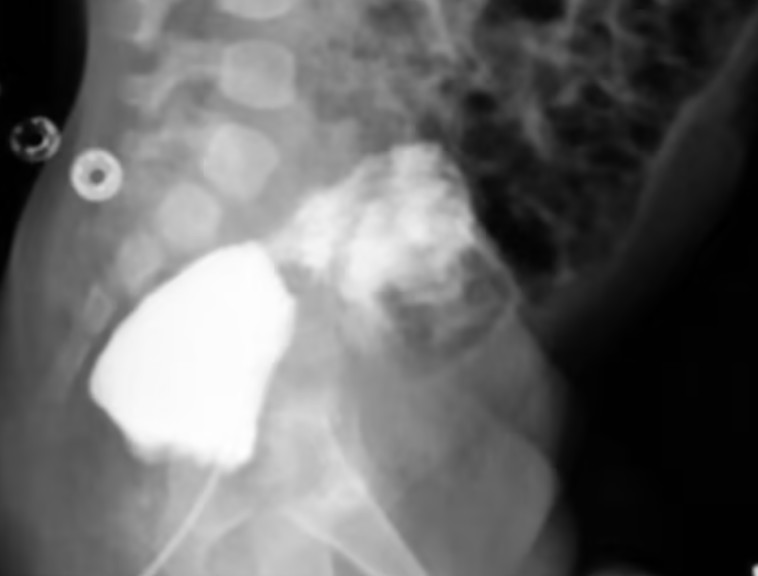

הרופאים טענו שהילד נולד בלידה תקינה ונמצא ב"מצב כללי טוב". אמו, ששמה גם אינו פורסם, לא דיווחה על בעיות במהלך ההריון. בדיקות מיוחדות שבוצעו חודשים לאחר שנולד, אפשרו לרופאים לברר כיצד פועלת מערכת השתן הייחודית שלו. הם גילו פיסטולה, חיבור לא תקין בין שלפוחית השתן שלו לפי הטבעת.